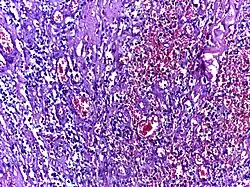

![]() | Tuberculous granuloma | Caseating granulomatous lesion with areas of amorphous granular eosinophilic necrotic debris known as caseation (on the right half) bordered by collections of epitheloid cells, Langhan giant cells and lymphocytes. | Category: Histopathology of tuberculous granuloma | Tuberculous granuloma |